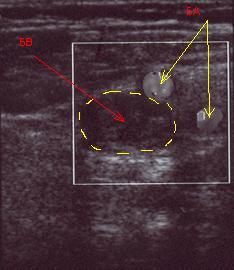

На сканограмме с цветным картированием запечатлен тромбоз бедренной вены. (на фото стрелка

красного цвета, в просвете гиперэхогенный массы, желтые стрелки обозначают артерии) у

больной обездвиженной вследствие заболевания центральной нервной системы. Артерии

прокрашиваются цветом, вена нет даже при компрессии. На этом уровне тромбоз

окклюзивный.